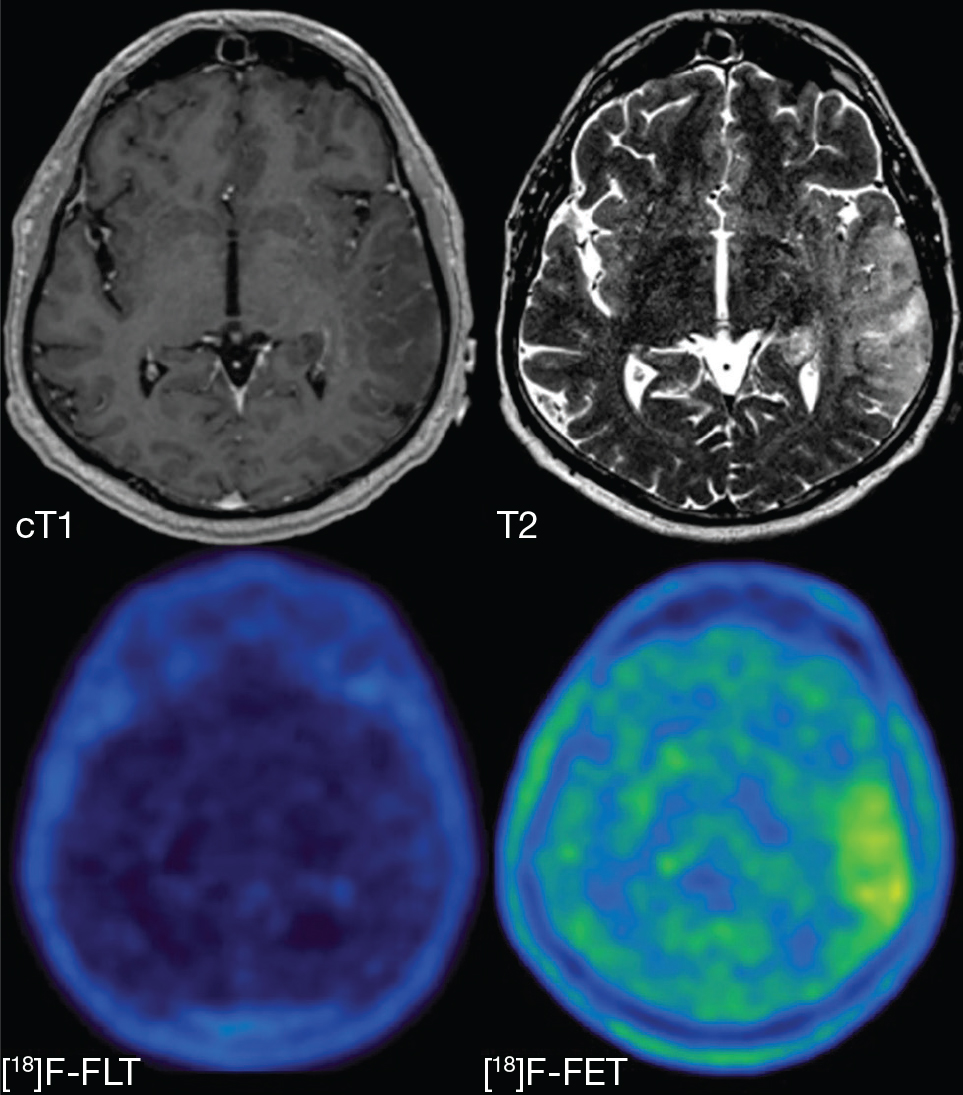

Fig 6

Figure 6. T1-weighted post-contrast (cT1), T2-weighted (T2), 18F-FLT PET ([18]F-FLT) and 18F-FET ([18]F-FET) images of a patient with a non-enhancing glioblastoma, WHO grade IV. The lesion is hyperintense on the T2-weighted image but does not show contrast enhancement. Increased uptake in the T2-hyperintense region can clearly be seen on the 18F-FET PET image, but there is no uptake visible on the 18F-FLT PET image, illustrating the drawback of PET agents that cannot easily cross the BBB. This figure is reproduced – with new figure legend appropriate for current article – from Nowosielski et al. (2014), Figure 1, under the terms of the Creative Commons Attribution 4.0 International (CC BY) License (http://creativecommons.org/licenses/by/4.0) (107).

68Ga-PSMA, 18F-DCFPyL and 89Zr-Df-IAB2M specifically bind to the prostate-specific membrane antigen (PSMA), a receptor thought to induce VEGF-independent angiogenesis in pathological conditions like tumors (Figure 7). PSMA is variably expressed on tumoral blood vessels and tumor cells depending on the tumor type, while no expression is seen on healthy brain parenchymal cells or normal vessels (Table 3); BBB transport will therefore depend on the tumor type (112). Preliminary studies showed high T/N ratios due to the virtually non-existent uptake in the healthy brain. Since all tested tumors showed contrast enhancement, this also raises the question whether uptake on PET images is not simply representative of increased BBB permeability without any role of PSMA. This hypothesis is strengthened by early reports on high uptake in enhancing radiation necrosis and ischemia (113, 114), although more recent studies have demonstrated the ability to distinguish recurrent high-grade gliomas from radiation necrosis (115). In clinical practice, with the limited data so far, uptake will likely reflect BBB permeability, overexpression of PSMA on endothelium or tumor cell (depending on tumor grade), or a combination of both. 68Ga-PSMA is used most often because of its extensive use in prostate cancer, while 18F-DCFPyL is similar but uses 18F as radionuclide. 89Zr-Df-IAB2M is a small part of the PSMA antibody and shows faster clearance, thereby achieving higher T/N ratios than the other two agents (116).